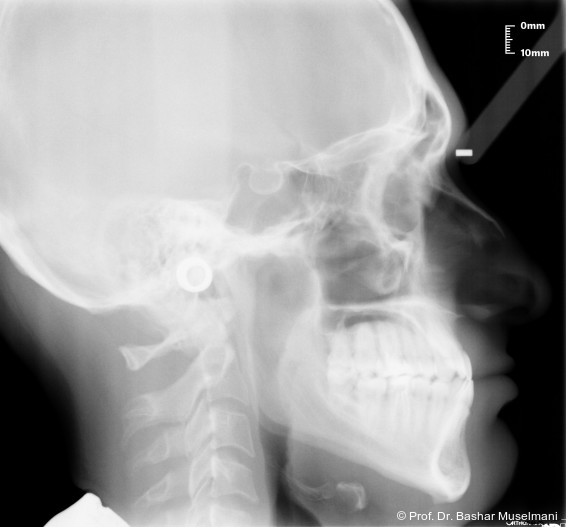

Fernröntgenologische Befunde (Behandlungsbeginn)

• SNA: 81,5°

• SNB: 84,3°

• ANB: −4,9°

• Wits-Wert: −8,4 mm

Klinische Befunde

• leicht konkaves Gesichts- und Mundprofil

• posterior positionierter Unterkiefer (VW)

• retroinkliniert stehende Unterkieferfront

Die Abbildungen 1 bis 3 zeigen die initiale klinische und radiologische Ausgangssituation.